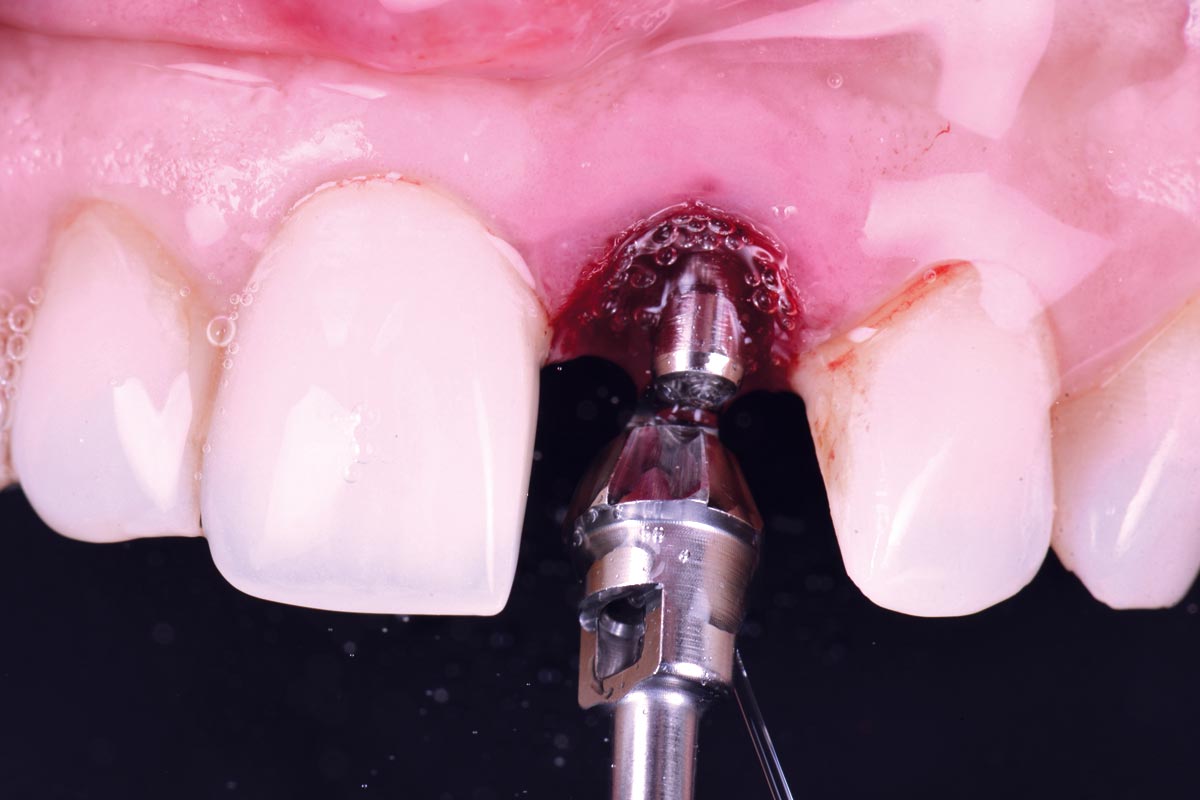

11/30 - Bone profiler was used to remove supracrestal boneExcellent aesthetic result of buccal augmentation with mucoderm® and maxgraft® after immediate implant placement - 3-years follow-up - Dr. A. Puišys